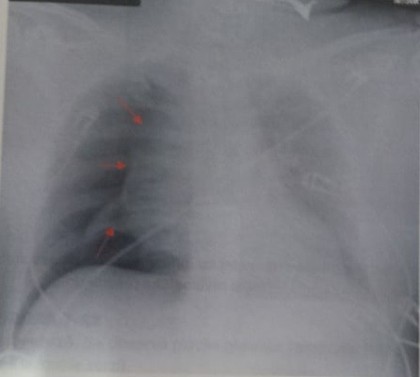

3. Pleurezia închistată mediastinal:

Apare ca o lărgire a mediastinului superior sau inferior cu aspect în bandă sau triunghiular, contur net, regulat.

Poate fi: totală (când lichidul ocupă etajul superior al spaţiului pleural mediastinal cât şi cele două camere ale etajului inferior – anterioară şi posterioară) sau parţială.

Pleurezia totală realizează o opacitate în bandă care transpare prin opacitatea mediastinală (cord, vase) sau care o depăşeşte lateral fiind net şi liniar conturată spre plămân. Conturul poate fi convex sau concav. Uneori, în dreptul hilului, colecţia în bandă poate fi îngustată de prezenţa pedicolului vascular şi opacitatea ia aspect „în ceas de nisip”.

Pleureziile închistate parţial pot fi:

- Pleureziile mediastinale inferioare: dau opacitate triunghiulară cu vârful la hil –triunghiul Chauffard-Rist care are o latură spre coloana vertebrală, alta spre diafragm şi ipotenuza spre transparenţa pulmonară. Radiografia de profil face diferenţierea între localizarea anterioară şi cea posterioară.

- Pleureziile mediastinale superioare sunt întâlnite mai rar în practică şi foarte rar izolate. Se traduc printr-o umbră juxtamediastinală care lărgeşte pediculul vascular, are formă vag triunghiulară şi coboară de la vârful plămânului până la hil.

Diagnosticul diferenţial al pleureziilor mediastinale trebuie făcut cu alte afecţiuni mediastinale: mediastinite, abcese, tumori mediastinale, anevrisme, ectazii vasculare, deplasări de organe mediastinale, dilataţii cardiace parţiale, adenopatii (au contur rotunjit, respectiv policiclic). Diagnosticul pozitiv de certitudine este computer tomografic.